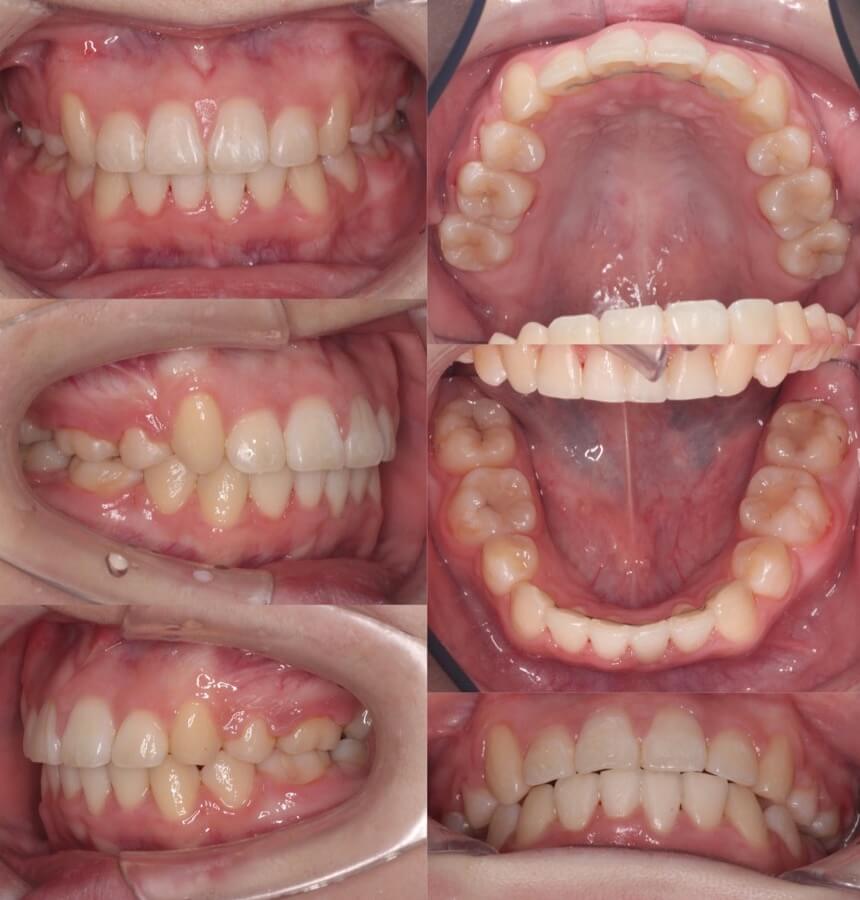

高校生女子・唇側矯正装置アンカースクリュー

<顔のビフォーアフター>

<症例概要>

主訴:でこぼこ

年齢・性別:高校生女子

住まい:千葉県八千代市

症状:著しい叢生

治療方針:上顎歯列後方移動・上下顎歯列拡大・ストリッピング

治療装置:唇側矯正装置

固定装置:歯科矯正用アンカースクリュー(口蓋側壁x2)・上下ポーター型拡大装置

抜歯:なし

治療期間:2年1か月

リテーナー:上下プレートタイプ+クリアタイプ下・フィックスタイプ

治療費用:968,000(税込)

代表的副作用:痛み・治療後の後戻り・歯根吸収・歯髄壊死・歯肉退縮

▶︎その他の副作用

著しいスペース不足による、上下顎歯列全体のデコボコです。アンカースクリューから上の奥歯を後方移動させ、歯に少しヤスリをかけて小さくするストリッピングを併用し、前歯を前に出すことなく矯正を完了する事ができました。治療後は素敵な笑顔になりました。